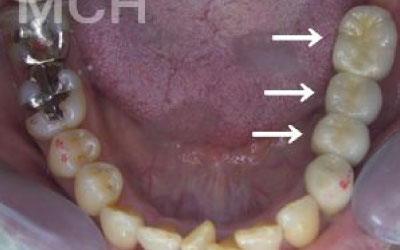

お口の状態や噛み合わせによって異なるため一概には言えませんが、一般的には奥歯が適しています。

特に、大臼歯(最も奥の歯)とその隣の歯がある部分です。

噛み合わせの力の60%以上がこの2本の歯で支えられているため、ここをインプラントでしっかり治療することは非常にお勧めです。